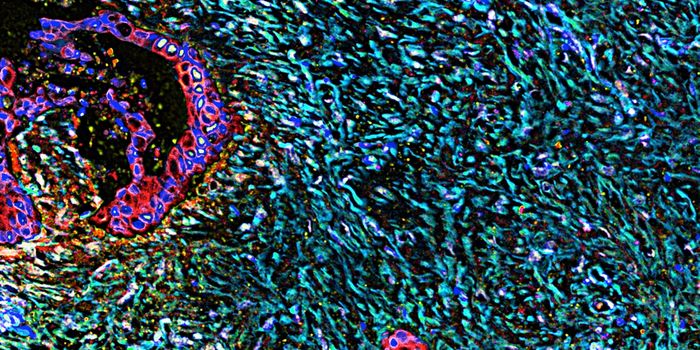

DEC 10, 2015ImmunologySuperior technology brings us novel images of cancer cells and lymphocytes this week, and now scientists can learn more ...